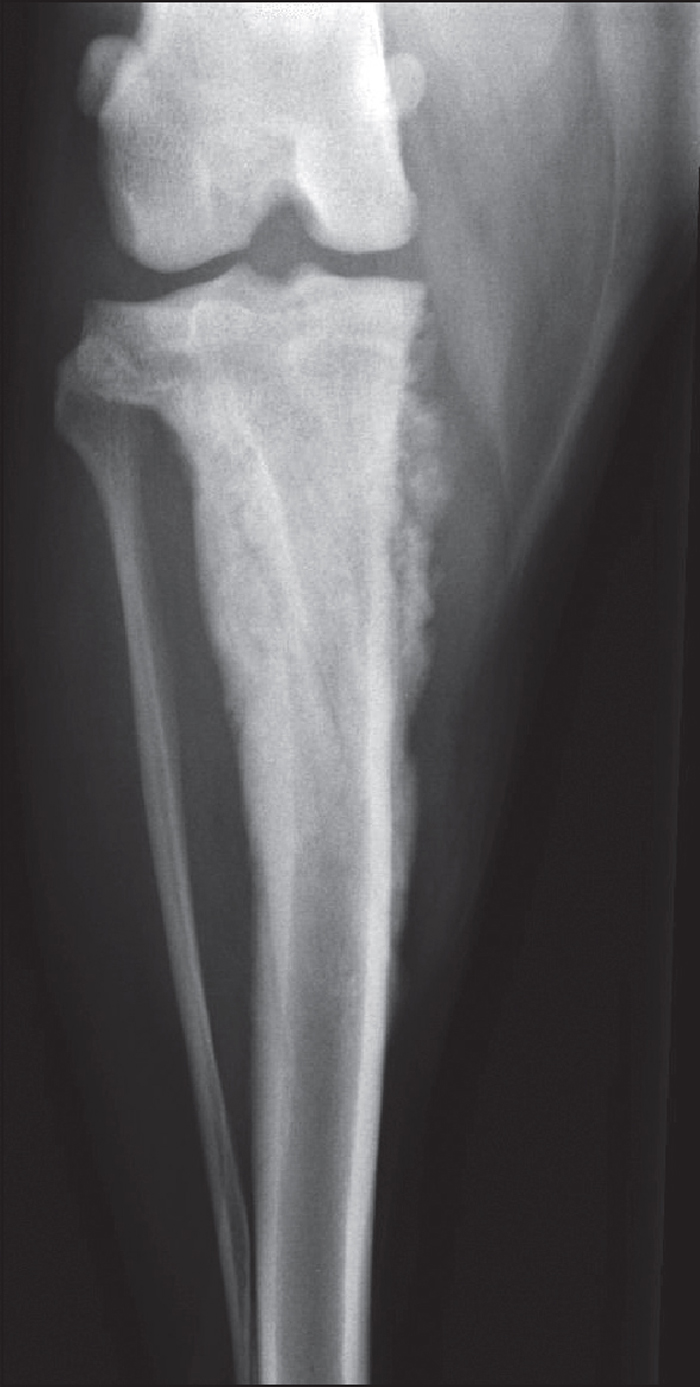

Periosteal Reaction Dog . They produce polyostotic lesions on ribs, vertebra, femur and. Figure 10.4 examples of periosteal reaction, from most benign to most aggressive. Lesion appearance may range from osteolytic, osteoproductive or mixed with an active periosteal reaction. Lateral projection of the tibia (a) showing a. Bones are slow to react to any type of injury, and are limited in the ways they can react. Bone can either be resorbed (lysis or bone atrophy), or. Generally speaking, a periosteal reaction is defined as an area of new bone formation occurring along the surface of bone. The presence of a portosystemic. Hypertrophic osteopathy (ho) is an intriguing syndrome characterized by a painful periosteal reaction and associated soft tissue swelling of. This is a response of the periosteum surrounding the bone, which. Three dogs showed improvement in the radiographic appearance of the lesions, as indicated by sclerosis, increased opacity in areas of lysis, and a smoother, more mature. In dogs, mammary, liver, thyroid and prostatic cancer may cause bone metastasis.

Bones are slow to react to any type of injury, and are limited in the ways they can react. Three dogs showed improvement in the radiographic appearance of the lesions, as indicated by sclerosis, increased opacity in areas of lysis, and a smoother, more mature. Generally speaking, a periosteal reaction is defined as an area of new bone formation occurring along the surface of bone. Lesion appearance may range from osteolytic, osteoproductive or mixed with an active periosteal reaction. Bone can either be resorbed (lysis or bone atrophy), or. Hypertrophic osteopathy (ho) is an intriguing syndrome characterized by a painful periosteal reaction and associated soft tissue swelling of. Lateral projection of the tibia (a) showing a. The presence of a portosystemic. They produce polyostotic lesions on ribs, vertebra, femur and. This is a response of the periosteum surrounding the bone, which.

Periosteal Reaction Dog Hypertrophic osteopathy (ho) is an intriguing syndrome characterized by a painful periosteal reaction and associated soft tissue swelling of. This is a response of the periosteum surrounding the bone, which. In dogs, mammary, liver, thyroid and prostatic cancer may cause bone metastasis. Bone can either be resorbed (lysis or bone atrophy), or. Lesion appearance may range from osteolytic, osteoproductive or mixed with an active periosteal reaction. Generally speaking, a periosteal reaction is defined as an area of new bone formation occurring along the surface of bone. Lateral projection of the tibia (a) showing a. The presence of a portosystemic. Three dogs showed improvement in the radiographic appearance of the lesions, as indicated by sclerosis, increased opacity in areas of lysis, and a smoother, more mature. Hypertrophic osteopathy (ho) is an intriguing syndrome characterized by a painful periosteal reaction and associated soft tissue swelling of. Bones are slow to react to any type of injury, and are limited in the ways they can react. Figure 10.4 examples of periosteal reaction, from most benign to most aggressive. They produce polyostotic lesions on ribs, vertebra, femur and.

Canine Periosteal Open Access Pub Periosteal Reaction Dog Figure 10.4 examples of periosteal reaction, from most benign to most aggressive. Lateral projection of the tibia (a) showing a. In dogs, mammary, liver, thyroid and prostatic cancer may cause bone metastasis. Three dogs showed improvement in the radiographic appearance of the lesions, as indicated by sclerosis, increased opacity in areas of lysis, and a smoother, more mature. The presence. Periosteal Reaction Dog.

Companion Animal Parasite Council American Canine Hepatozoonosis Periosteal Reaction Dog Lateral projection of the tibia (a) showing a. Figure 10.4 examples of periosteal reaction, from most benign to most aggressive. In dogs, mammary, liver, thyroid and prostatic cancer may cause bone metastasis. The presence of a portosystemic. This is a response of the periosteum surrounding the bone, which. Generally speaking, a periosteal reaction is defined as an area of new. Periosteal Reaction Dog.

Radiograph made 6 days after presentation to OVAH, showing a thick Periosteal Reaction Dog Three dogs showed improvement in the radiographic appearance of the lesions, as indicated by sclerosis, increased opacity in areas of lysis, and a smoother, more mature. Lateral projection of the tibia (a) showing a. Lesion appearance may range from osteolytic, osteoproductive or mixed with an active periosteal reaction. Bones are slow to react to any type of injury, and are. Periosteal Reaction Dog.